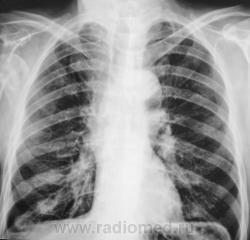

Перелом шейки правой плечевой кости вижу. Свежих переломов ребер и пневмоторакса не вижу. Справа - старые переломы. Но, честно говоря, видно плохо - снимки почему-то не увеличиваются...

Вы правы, структура не нормальна, есть довольно четкие очаги. Аналогичный очаг в суставном отростке лопатки, да и структура задних отрезков 9-10 ребер справа настораживает. Перелом плеча, если он действительно свежий, то скорее всего - патологический. Но! А травмы кисти и л/з сустава не было?

Лаборанты "усекли", что что-то не в порядке с головкой плечевой кости и с самой плечевой костью и решили дополнительно сделать рентгенограмму сустава.

Похоже тоже старый неконсолидорованый переломовывих. А переломов ребер и тут не вижу...

Перелом, по всей видимости, не старый, травма 2 дня тому, но "клиент" находился в подпитии.

Большой интерес, конечно, представляет "ручка", левая клиента. Какой-то уж сильно странненький остеопороз.